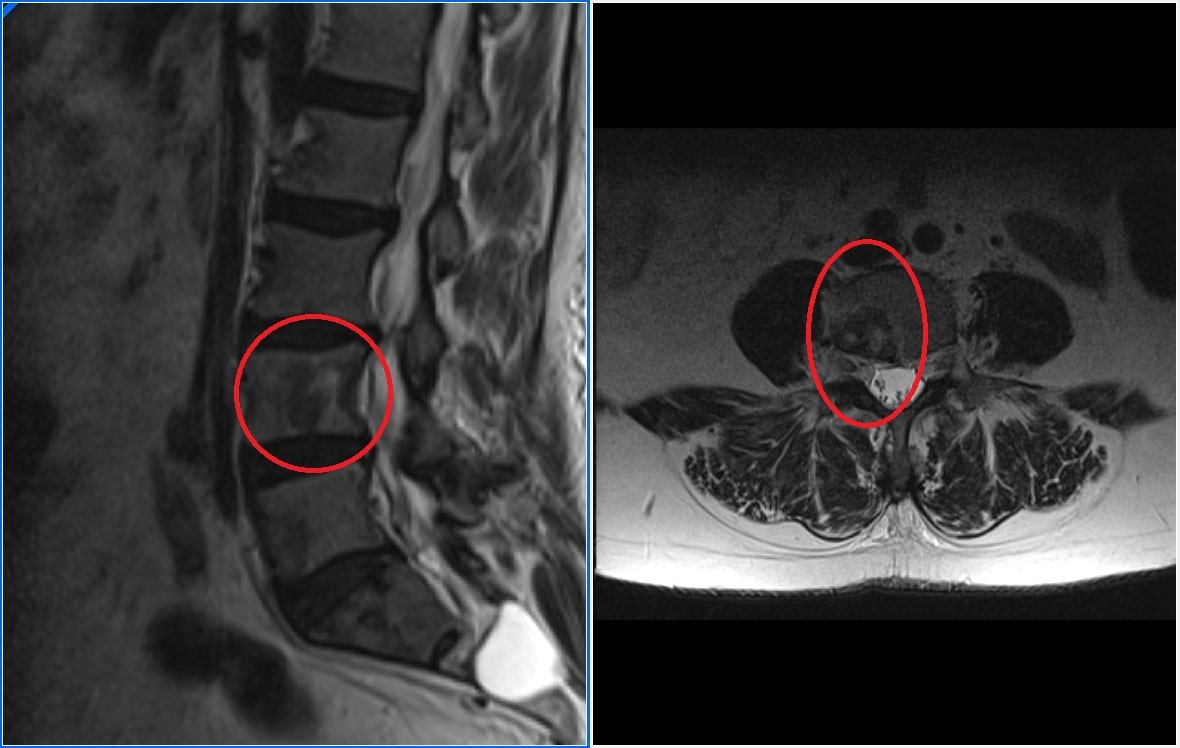

La clínica neurológica se produce al aumentar el tamaño de la metástasis vertebral y comprimir las estructuras nerviosas. Es una clínica muy variable y depende del lugar donde este situada la lesión, puede producir una radiculopatía, alteraciones motores, sensitivas o de esfínteres. Normalmente aparecen antes las alteraciones sensitivas, las metástasis suelen comprimir primero la parte anterior de la médula que es por donde discurren las fibras nerviosas sensitivas. El caso más grave es la compresión medular, en la que los pacientes pueden presentar paraplejia rápidamente progresiva, esta situación es una urgencia quirúrgica.

Síntomas neurológicos. Otro objetivo de la cirugía ha de ser evitar o mejorar los síntomas neurológicos. Para ellos en ocasiones es necesario realizar laminectomias y descompresiones medulares. El pronóstico vital empeora mucho cuando un paciente que tienen una enfermedad metastásica no es capaz de caminar. Una complicación neurológica especial es la compresión medular, se trata de una urgencia quirúrgica ya que cuanto más tiempo este la médula comprimida menos posibilidades tenemos para que un paciente se recupere y vuelva andar. Tienen mejor pronóstico las compresiones medulares incompletas y que no progresen rápidamente.